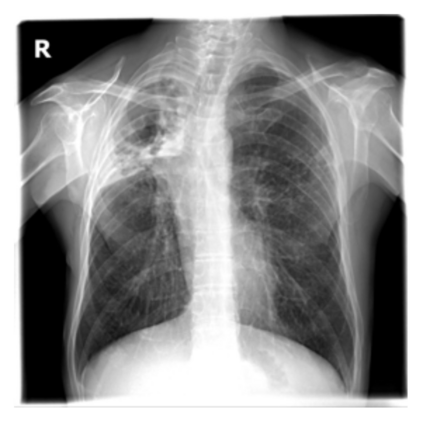

The evaluation of infectious disease processes on radiologic images is an important and challenging task in medical image analysis. Pulmonary infections can often be best imaged and evaluated through computed tomography (CT) scans, which are often not available in low-resource environments and difficult to obtain for critically ill patients. On the other hand, X-ray, a different type of imaging procedure, is inexpensive, often available at the bedside and more widely available, but offers a simpler, two dimensional image. We show that by relying on a model that learns to generate CT images from X-rays synthetically, we can improve the automatic disease classification accuracy and provide clinicians with a different look at the pulmonary disease process. Specifically, we investigate Tuberculosis (TB), a deadly bacterial infectious disease that predominantly affects the lungs, but also other organ systems. We show that relying on synthetically generated CT improves TB identification by 7.50% and distinguishes TB properties up to 12.16% better than the X-ray baseline.